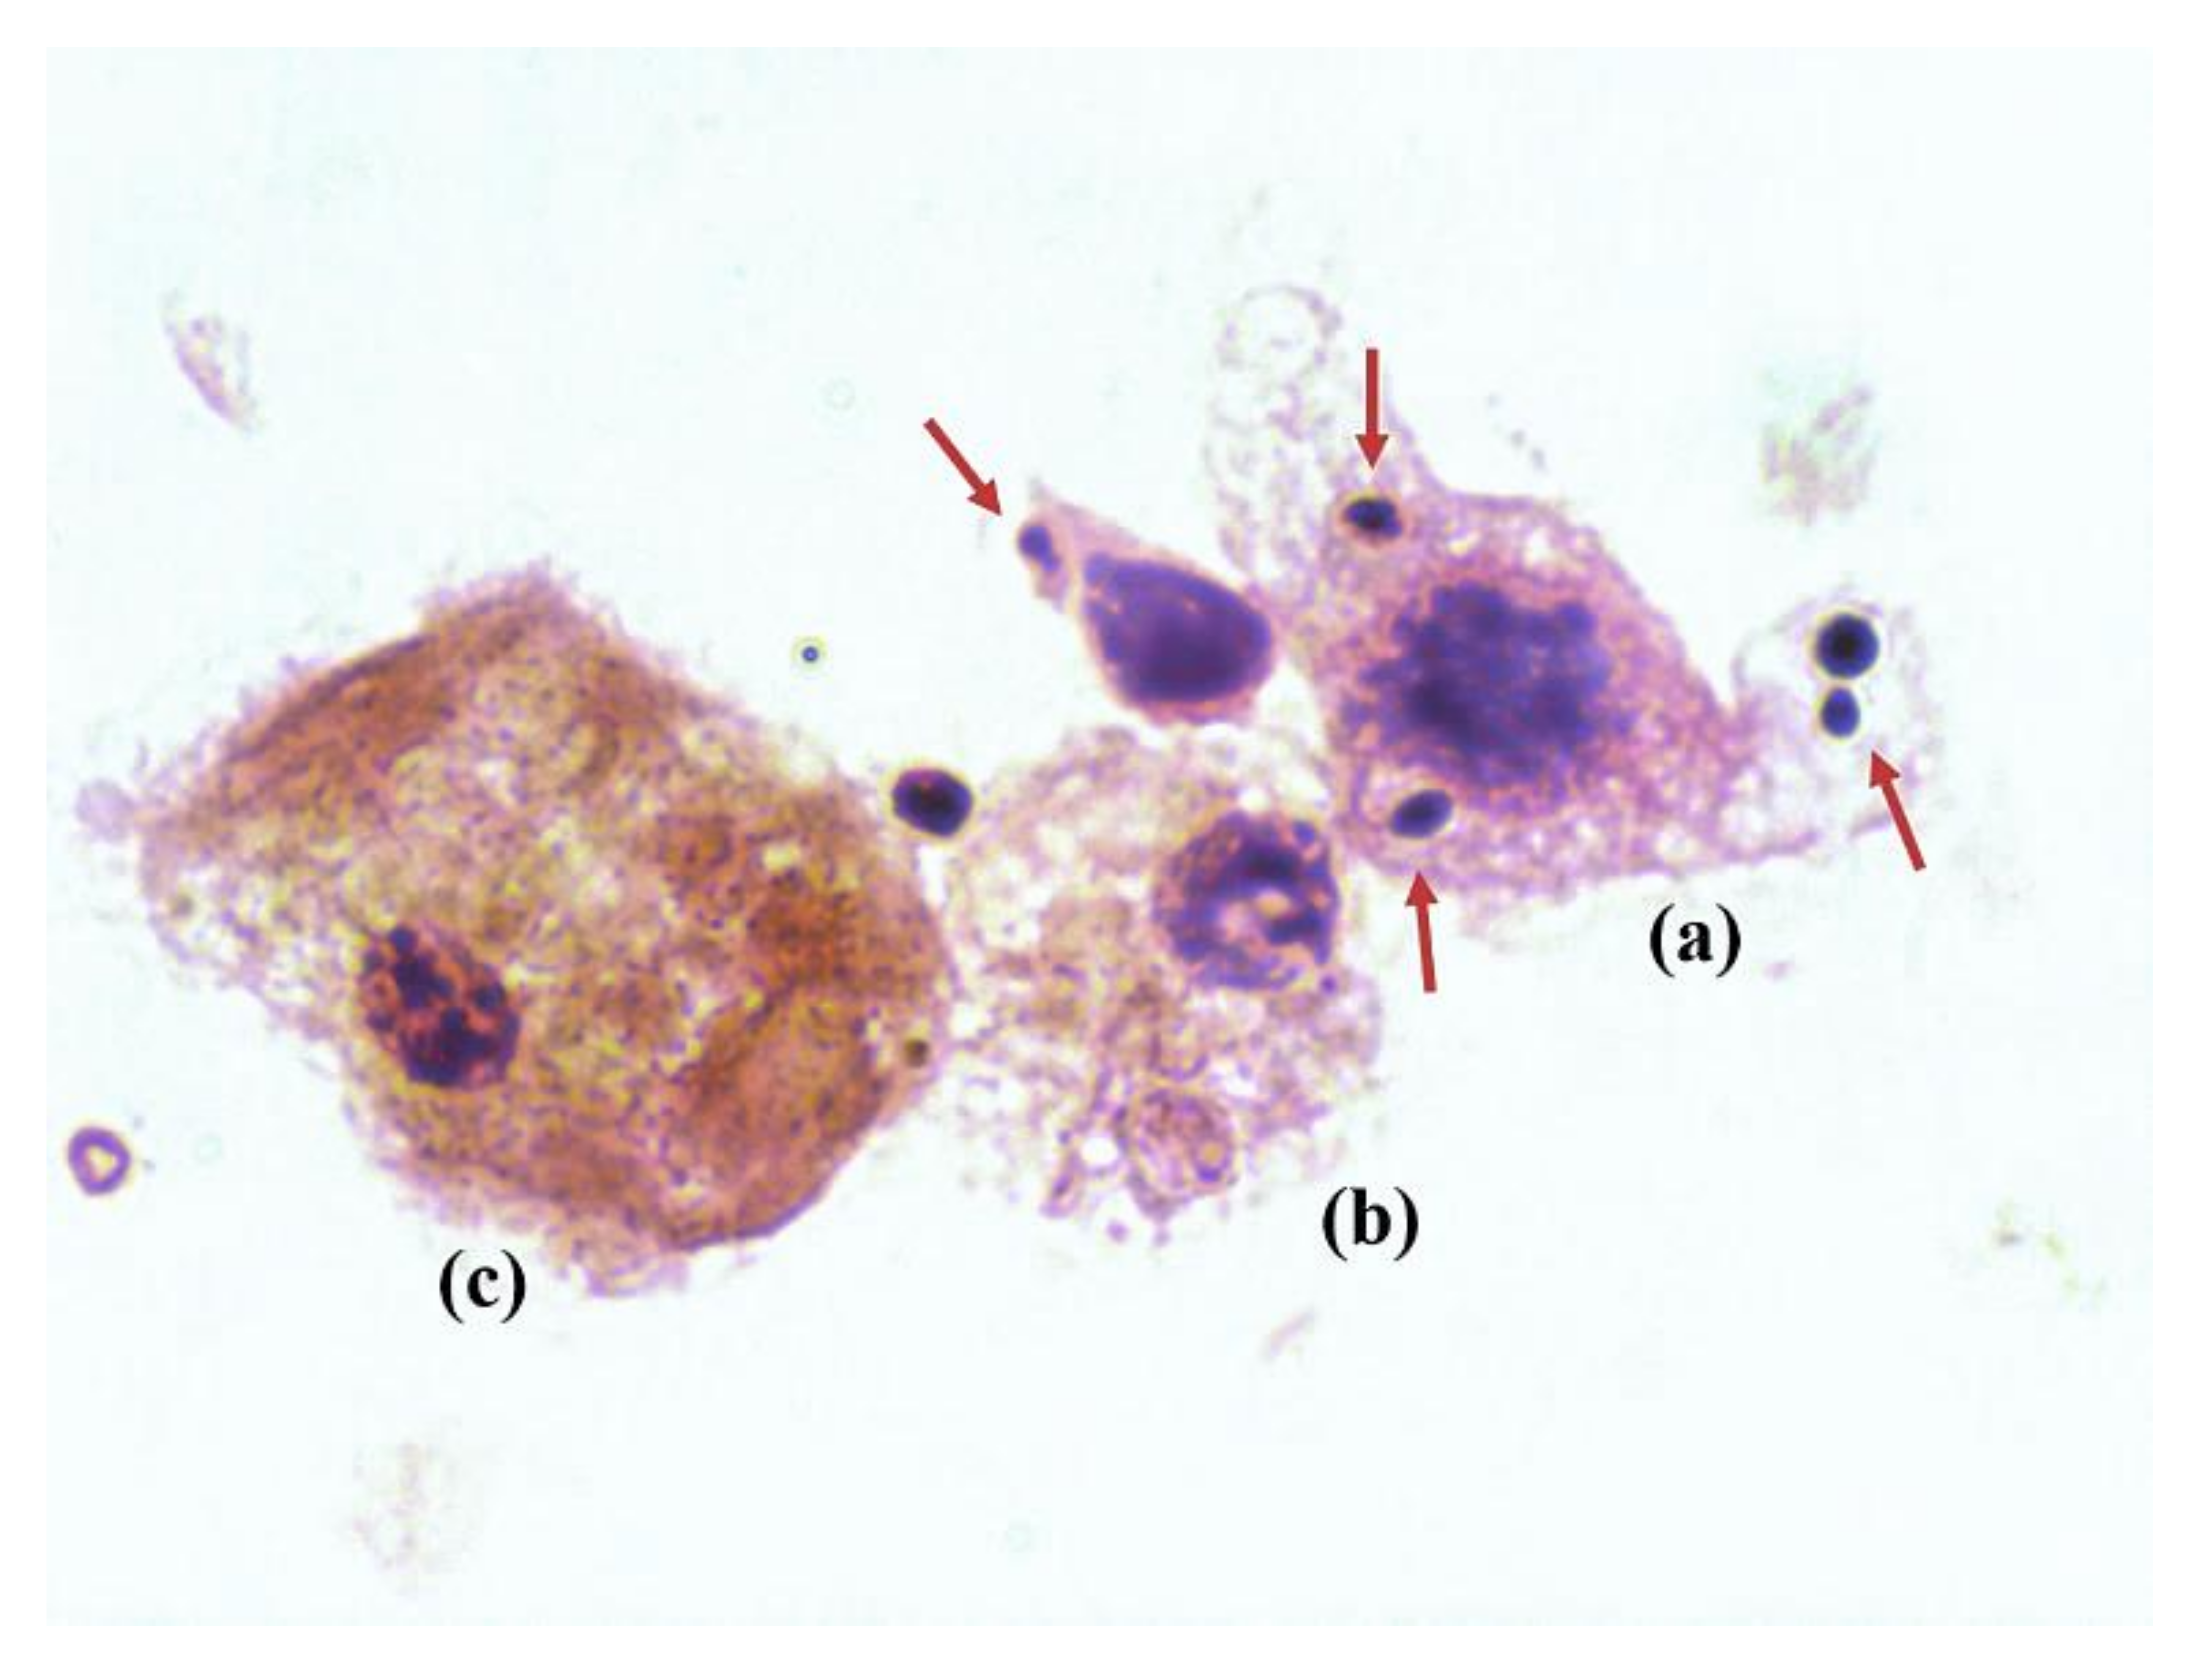

2.2. Microbiological and Pathological Results

4.3. Microbiological and Pathological Studies

- PJI was diagnosed when any type of osteomyelitis and the presence of yeast were evidenced.